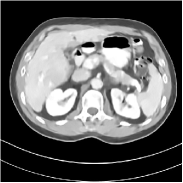

This special case of SUPER corresponds to the case where SUPER excludes the unsupervised regularizer, while only involves the data-fidelity and a supervised regularizer in the MBIR cost, i.e., β=0𝛽0\beta=0 and μ0𝜇0\mu\neq 0. In this case, the proposed SUPER model is similar to a generalized block coordinate descent-based network by replacing a simple denoising autoencoder [28, 29, 30] with a general CNN that forms our supervised regularizer. This SUPER is also similar to the plug-and-play ADMM-Net method except that the inputs to each supervised network are the preceding reconstructions, while plug-and-play ADMM-Net updates inputs to the network (denoiser) based on auxiliary variables in the ADMM algorithm. Here, we used μ=1×106𝜇1superscript106\mu=1\times 10^{6}, which worked well for the plug-and-play ADMM-Net method, for this special case of SUPER. Fig. 7 shows a comparison between plug-and-play ADMM-Net, SUPER without unsupervised regularizers (in both training and testing), and the full SUPER version with ULTRA regularization (β=5×103𝛽5superscript103\beta=5\times 10^{3}, μ=5×105𝜇5superscript105\mu=5\times 10^{5}). All these methods used WavResNet as their denoisers/supervised networks. In this example, SUPER with only a supervised regularizer (SUPER-WRN-β=0𝛽0\beta=0) outperforms the plug-and-play ADMM-Net (ADMM-Net (WRN)) by 1.6 HU RMSE and provides sharper image details. Comparing SUPER-WRN-β=0𝛽0\beta=0 and the full SUPER-WRN-ULTRA scheme, we observe that the latter provides a lower RMSE and higher contrast image features than the former that excludes the unsupervised component. This again shows the effect of the unsupervised ULTRA model (in capturing local image details better with a union of learned transforms) in the SUPER scheme.

Refer to captionADMM-Net (WRN)RMSE = 32.90 HURefer to captionADMM-Net (WRN)RMSE = 32.90 HU

Refer to captionSUPER-WRN-β=0𝛽0\beta=0RMSE = 31.32 HURefer to captionSUPER-WRN-β=0𝛽0\beta=0RMSE = 31.32 HU

Refer to caption SUPER-WRN-ULTRARMSE = 29.74 HURefer to caption SUPER-WRN-ULTRARMSE = 29.74 HU

Refer to caption ReferenceRefer to caption Reference

Figure 7: Reconstructed images of L192 slice 150 with WavResNet plugged ADMM-Net, SUPER-WRN-β=0𝛽0\beta=0 (both training and testing), and SUPER-WRN-ULTRA (β=5×103𝛽5superscript103\beta=5\times 10^{3} in both training and testing), respectively, shown with the reference image.